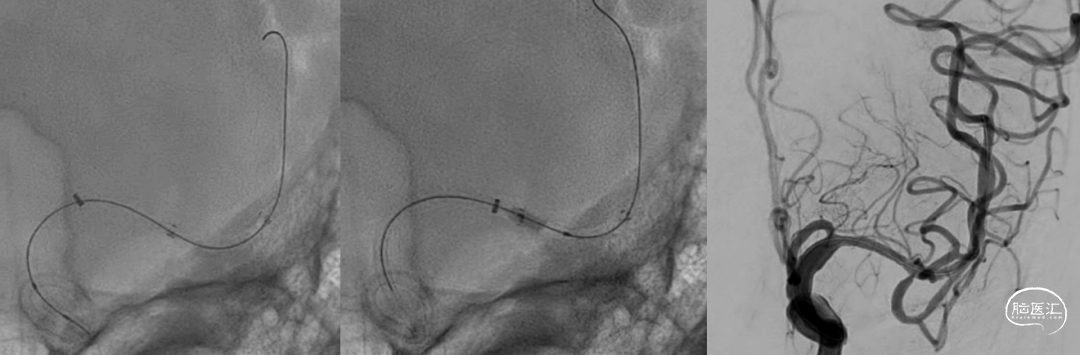

8F血管鞘,8F-指引导管,泥鳅导丝

Sofia(125cm,6F)远端通路导管

Synchro-14(3m)微导丝

加奇SacSpeed® 2mm×9mm颅内球囊

8F指引勾选左侧颈内动脉,推送Sofia导管至左侧大脑中动脉闭塞段近端;Sofia导管抽除少量团块样血栓,闭塞段血运复通,责任病变段血管重度狭窄。

Synchro-14微导丝留置于左侧大脑中动脉下干远端分支建立轨道;沿导丝送入加奇SacSpeed® 2mm×9mm颅内球囊,造影定位于狭窄段。

加奇SacSpeed® 2mm×9mm颅内球囊缓慢充盈成形扩张原位狭窄段;经球扩后,责任病变血管狭窄程度明显改善,前向血运流速改善。